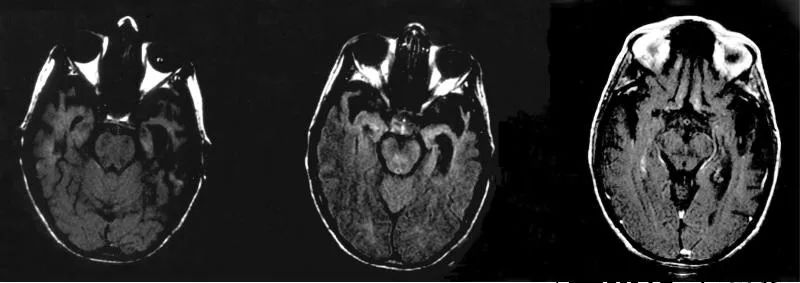

早期的神經影像學研究發現了很多CS 患者的左顳頂葉和右顳葉有損傷(並非全部都是這樣)。2004年後其他研究發現CS 患者其他特定腦區(主要是額頂葉皮質、基底神經節和丘腦) 有明顯改變,經過治療後部分症狀緩解。

一位科塔爾症患者的顳頂聯合區磁共振成像顯示雙側顳葉前部萎縮 (圖片來源:pmc)

比如説當沃倫看到自己的妻子,他會承認那個人看起來確實像他的妻子,但是人在遇見熟人,尤其是愛人時的那種温馨的感覺,他卻一點都體會不到。這種在情緒和感官之間的斷裂延伸到了他生活的各種體驗之中。